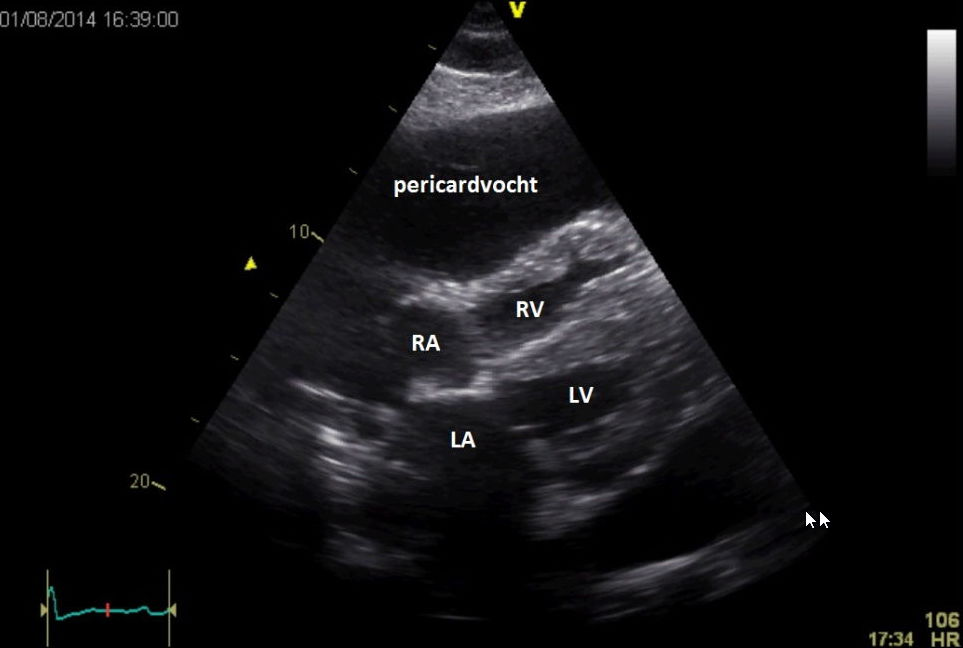

Figuur D: echocardiografie pericardeffusie